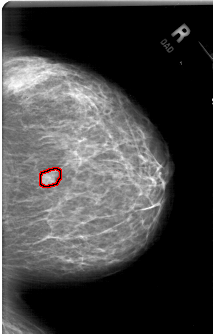

A_1779_1.RIGHT_MLO

RIGHT_MLO LINES 6406 PIXELS_PER_LINE 4021 BITS_PER_PIXEL 12 RESOLUTION 43.5 OVERLAY

FILE: A_1779_1.RIGHT_MLO.OVERLAY

TOTAL_ABNORMALITIES 1

ABNORMALITY 1

LESION_TYPE MASS SHAPE LOBULATED MARGINS ILL_DEFINED

ASSESSMENT 4

SUBTLETY 3

PATHOLOGY BENIGN

TOTAL_OUTLINES 1

BOUNDARY